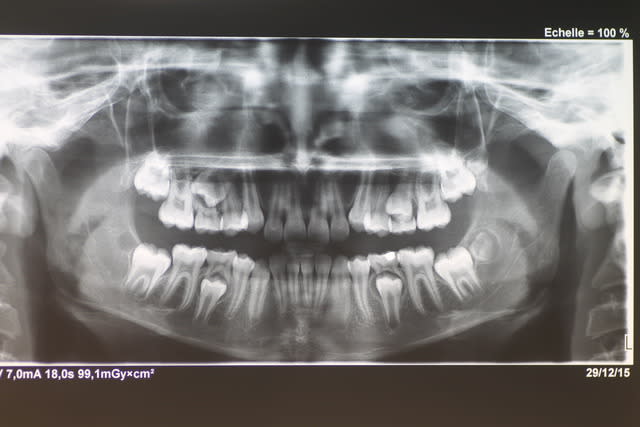

Il faudrait plus d'éléments pour répondre ( télé profil, pano, photos endo et exo buccales)

quelques documents :

t'as vu la 37 ? dommage , on ne la voit pas en occlusion mais rien qu'a voir la tronche qu'elle a ....

il est bloqué un peu vers l'avant ,mais surtout avec la drete mesiale de 37 qui n'est pas alignée , il ne peut meme pas retropulser du coté gauche .alors il serre a gauche et comme la 37 est couchée ça lui donne un decalage lateral posterieur .

C'est pas la 37,c'est la 36!

T ain oui la 36 :-)))